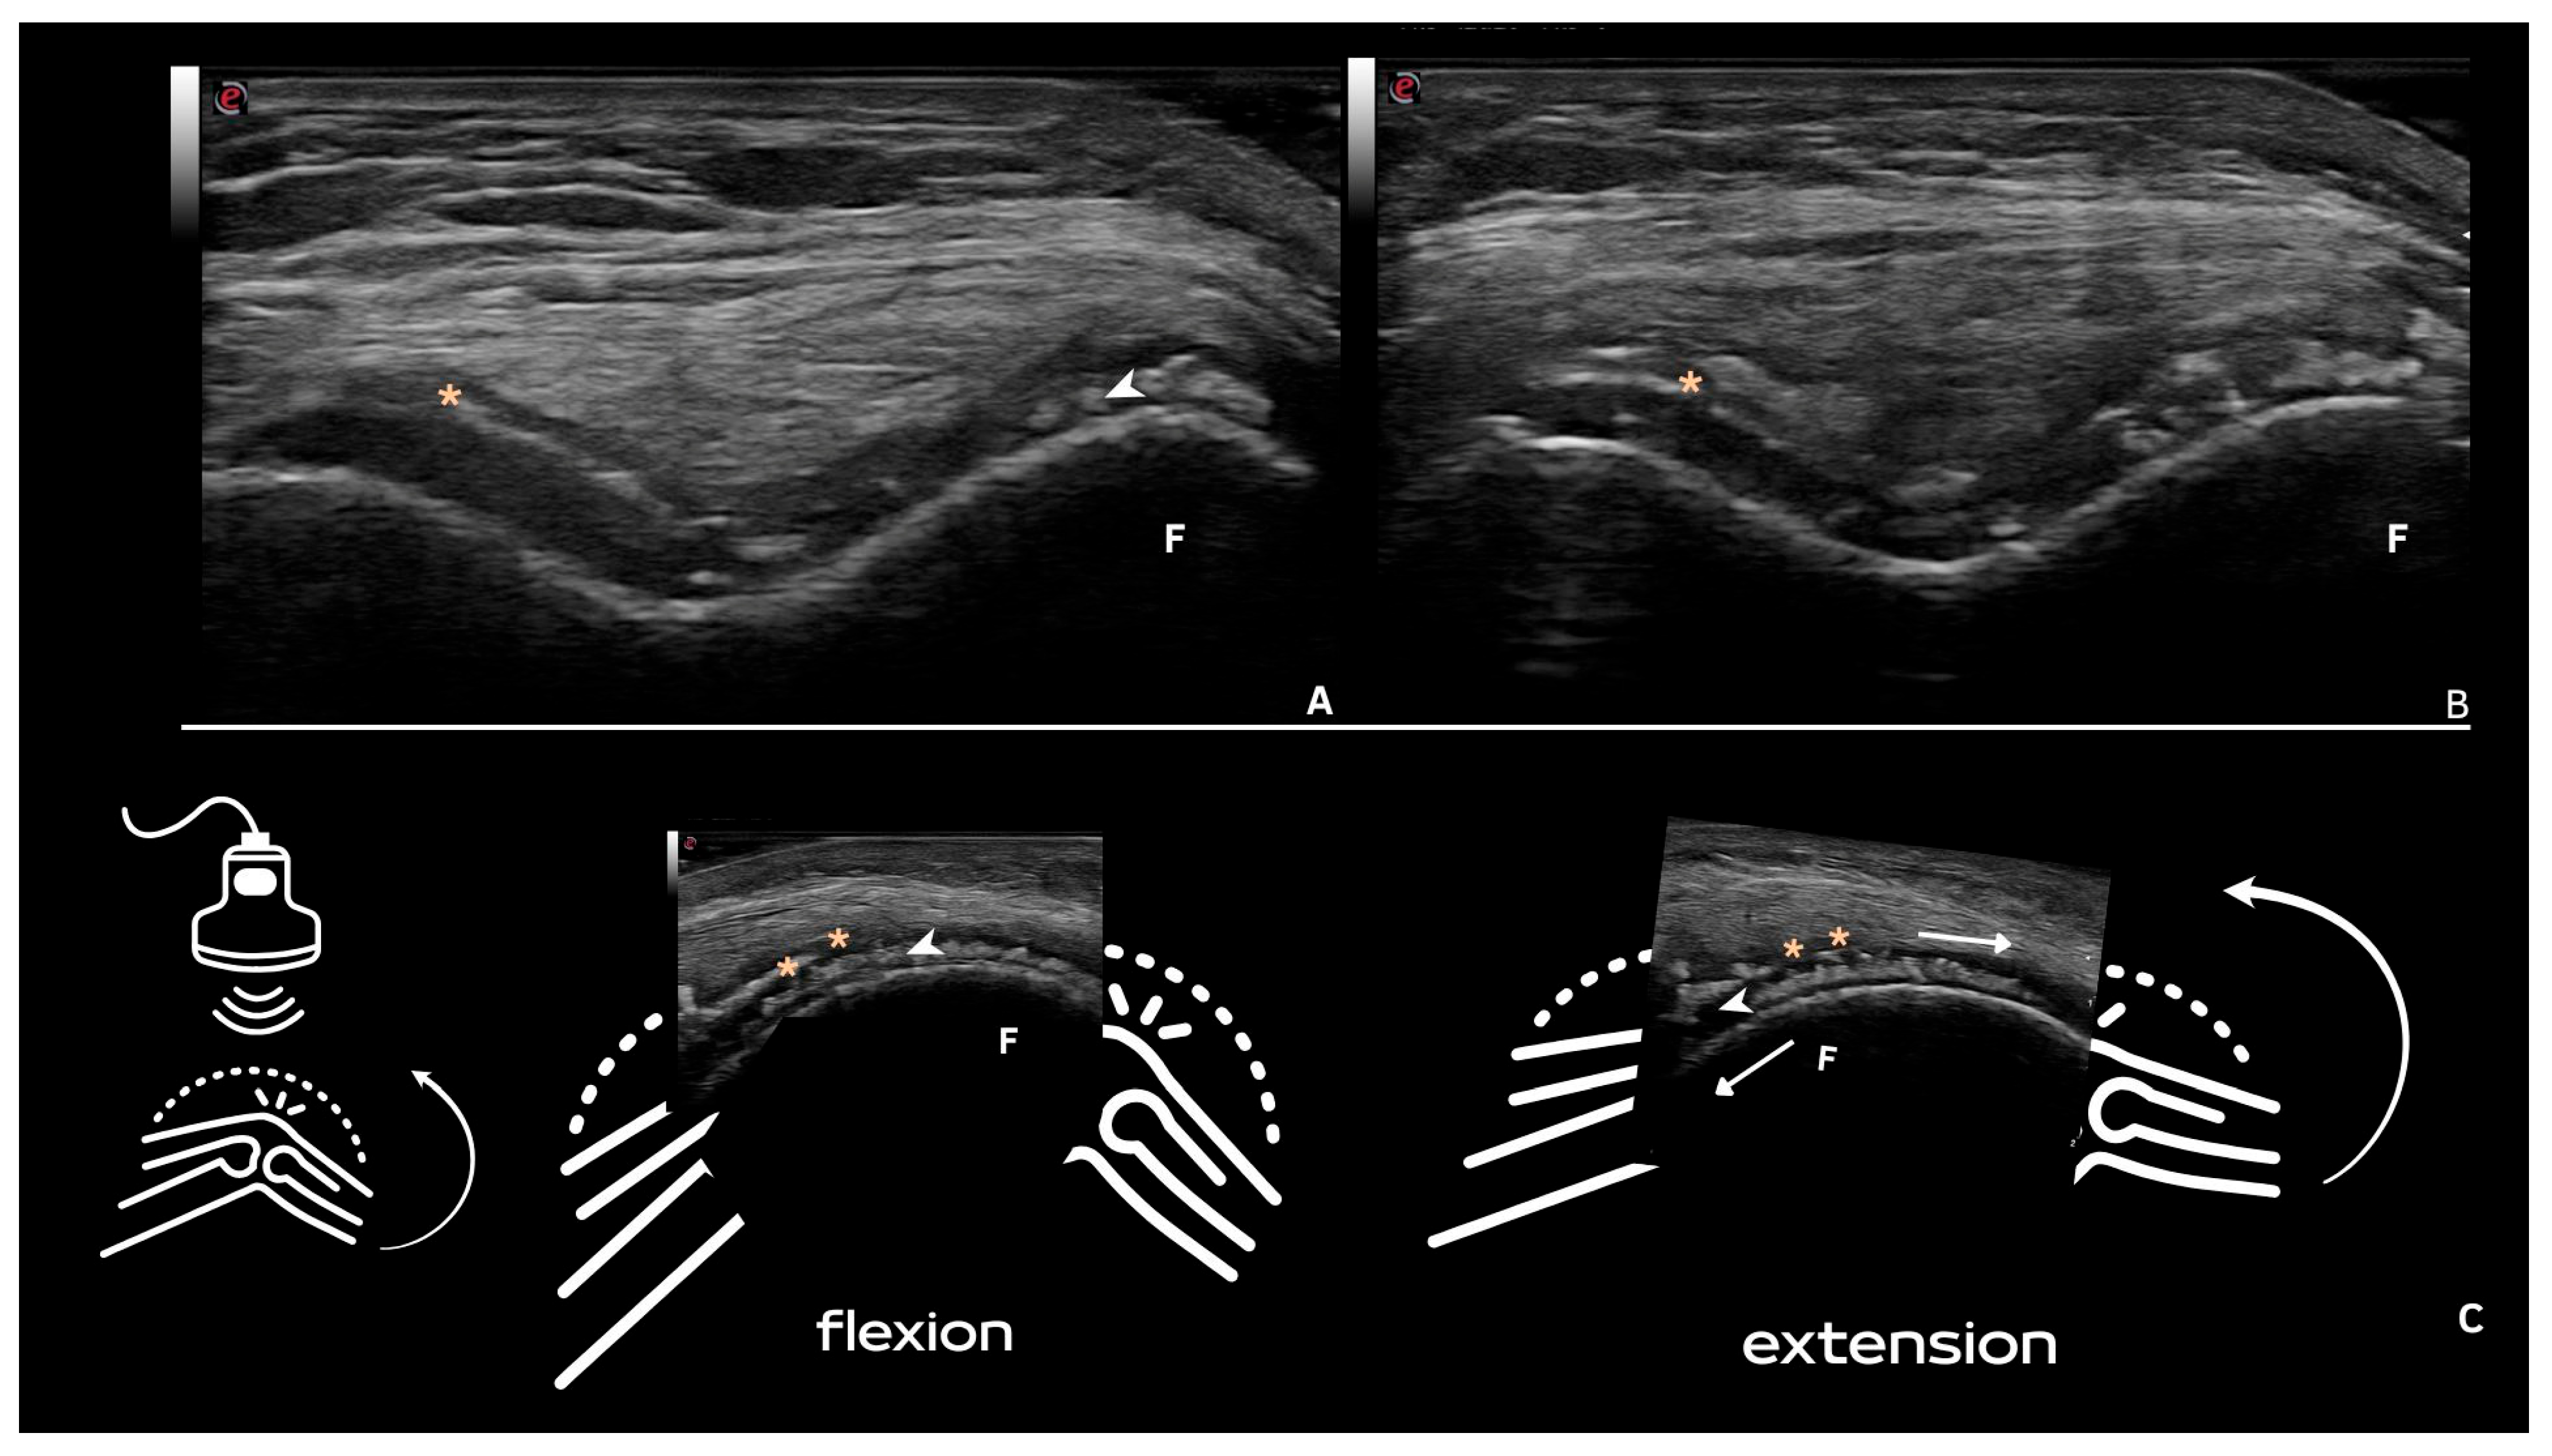

| Hyaline cartilage | Shape: Deposits of variable shape. Echogenicity: Hyperechoic, without posterior shadowing. Localization: Localized within the hyaline cartilage. Dynamic scanning: The deposits remain fixed and move together with the hyaline cartilage. Examples: Knee and MCP joint. |

| Pseudo-double contour sign | Shape: Deposits of variable shape. Echogenicity: Hyperechoic, without posterior shadowing. Localization: Localized at the chondro-synovial interface or in the joint capsule and adjacent ligaments. Dynamic scanning: Moves in the opposite direction of cartilage and adjacent bone. Examples: Knee, proximal, and distal radio-ulnar joint. |